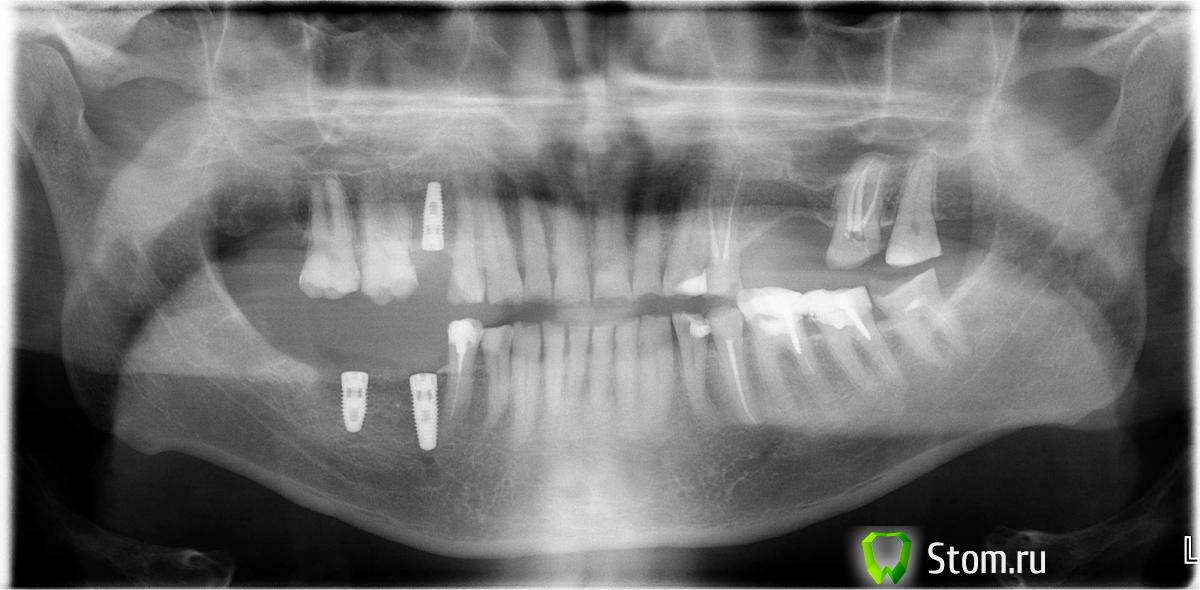

alecx Опубликовано 31 марта, 2012 Поделиться Опубликовано 31 марта, 2012 Прошу помочь развеять мои сомнения в неправильности установки имплантов на нижней челюсти. Снимок прилагается.1. Кажется оба импланта нужно было сместить чуть-чуть левее (дальше от зубов). Возможно из-за такой постановки вся тяжесть жевательной работы ляжет на последний имплант и он может не выдержать.2. Доктор говорит, что проблем не будет. Но по здравому смыслу при такой установке нужно ставить еще один имплант на самый край челюсти или может быть между двух уже установленных имплантов.3. Или проще переустановить имплант, который ближе к зубу. Импланты установлены сегодня.4. Волнует больше всего в дальнейшем эксплуатационная надежность. Спасибо всем ответившим. Ссылка на комментарий

Bier Опубликовано 31 марта, 2012 Поделиться Опубликовано 31 марта, 2012 нормально все стоит. Дальше по челюсти могут быть анатомические ограничения. Ссылка на комментарий

Большой Зеленый Опубликовано 31 марта, 2012 Поделиться Опубликовано 31 марта, 2012 нормально все стоит. Дальше по челюсти могут быть анатомические ограничения.+1 займитесь лучще лечением левой стороны . Зубы надо перелечивать. Ссылка на комментарий

alecx Опубликовано 15 апреля, 2012 Автор Поделиться Опубликовано 15 апреля, 2012 Вопрос по нижней шестерке с левой стороны.Её можно перелечить или только удалять, с последующим установлением импланта? Ссылка на комментарий

Bier Опубликовано 15 апреля, 2012 Поделиться Опубликовано 15 апреля, 2012 можно попробовать полечить. Ссылка на комментарий